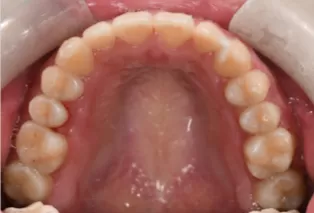

Intraoral photos